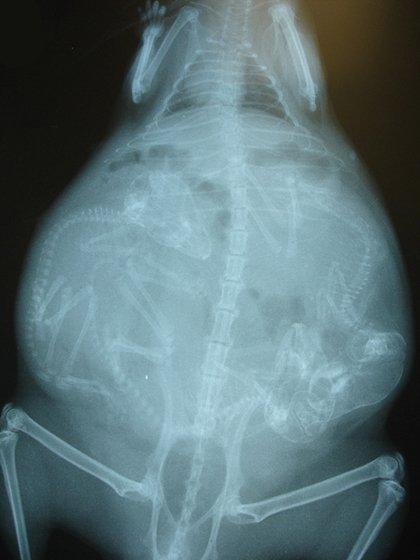

哈~這其實是動物懷孕的照片啦!美國《boredpanda》網站最近整理了一系列懷孕動物的X光照,從最常被人類飼養的貓、狗,乃至於蝙蝠、浣熊等都有,雖然小動物的誕生應該是可愛而溫馨,不過單看這些滿肚骨骸的X光照,還是覺得有點驚悚和詭異啊!

天竺鼠